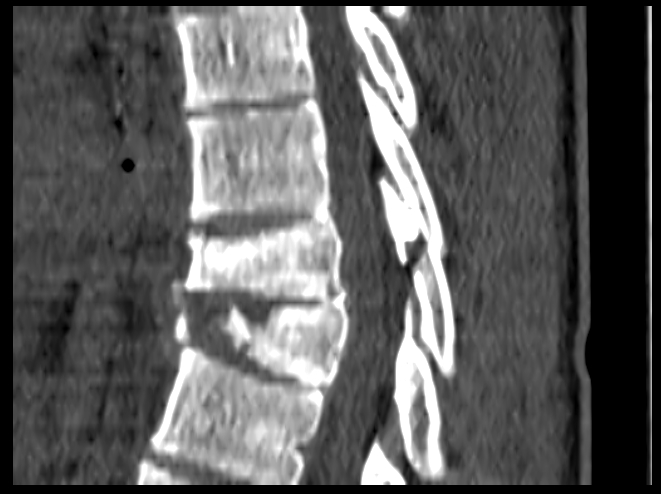

Воткнулся головой

Недолетел верблюда - не хватило скорости, рухнул как мешок с г..ном.

Полтора месяца в койке, почти три - в корсете и нельзя ничего.

В итоге не срастается и будут ставить пластину.